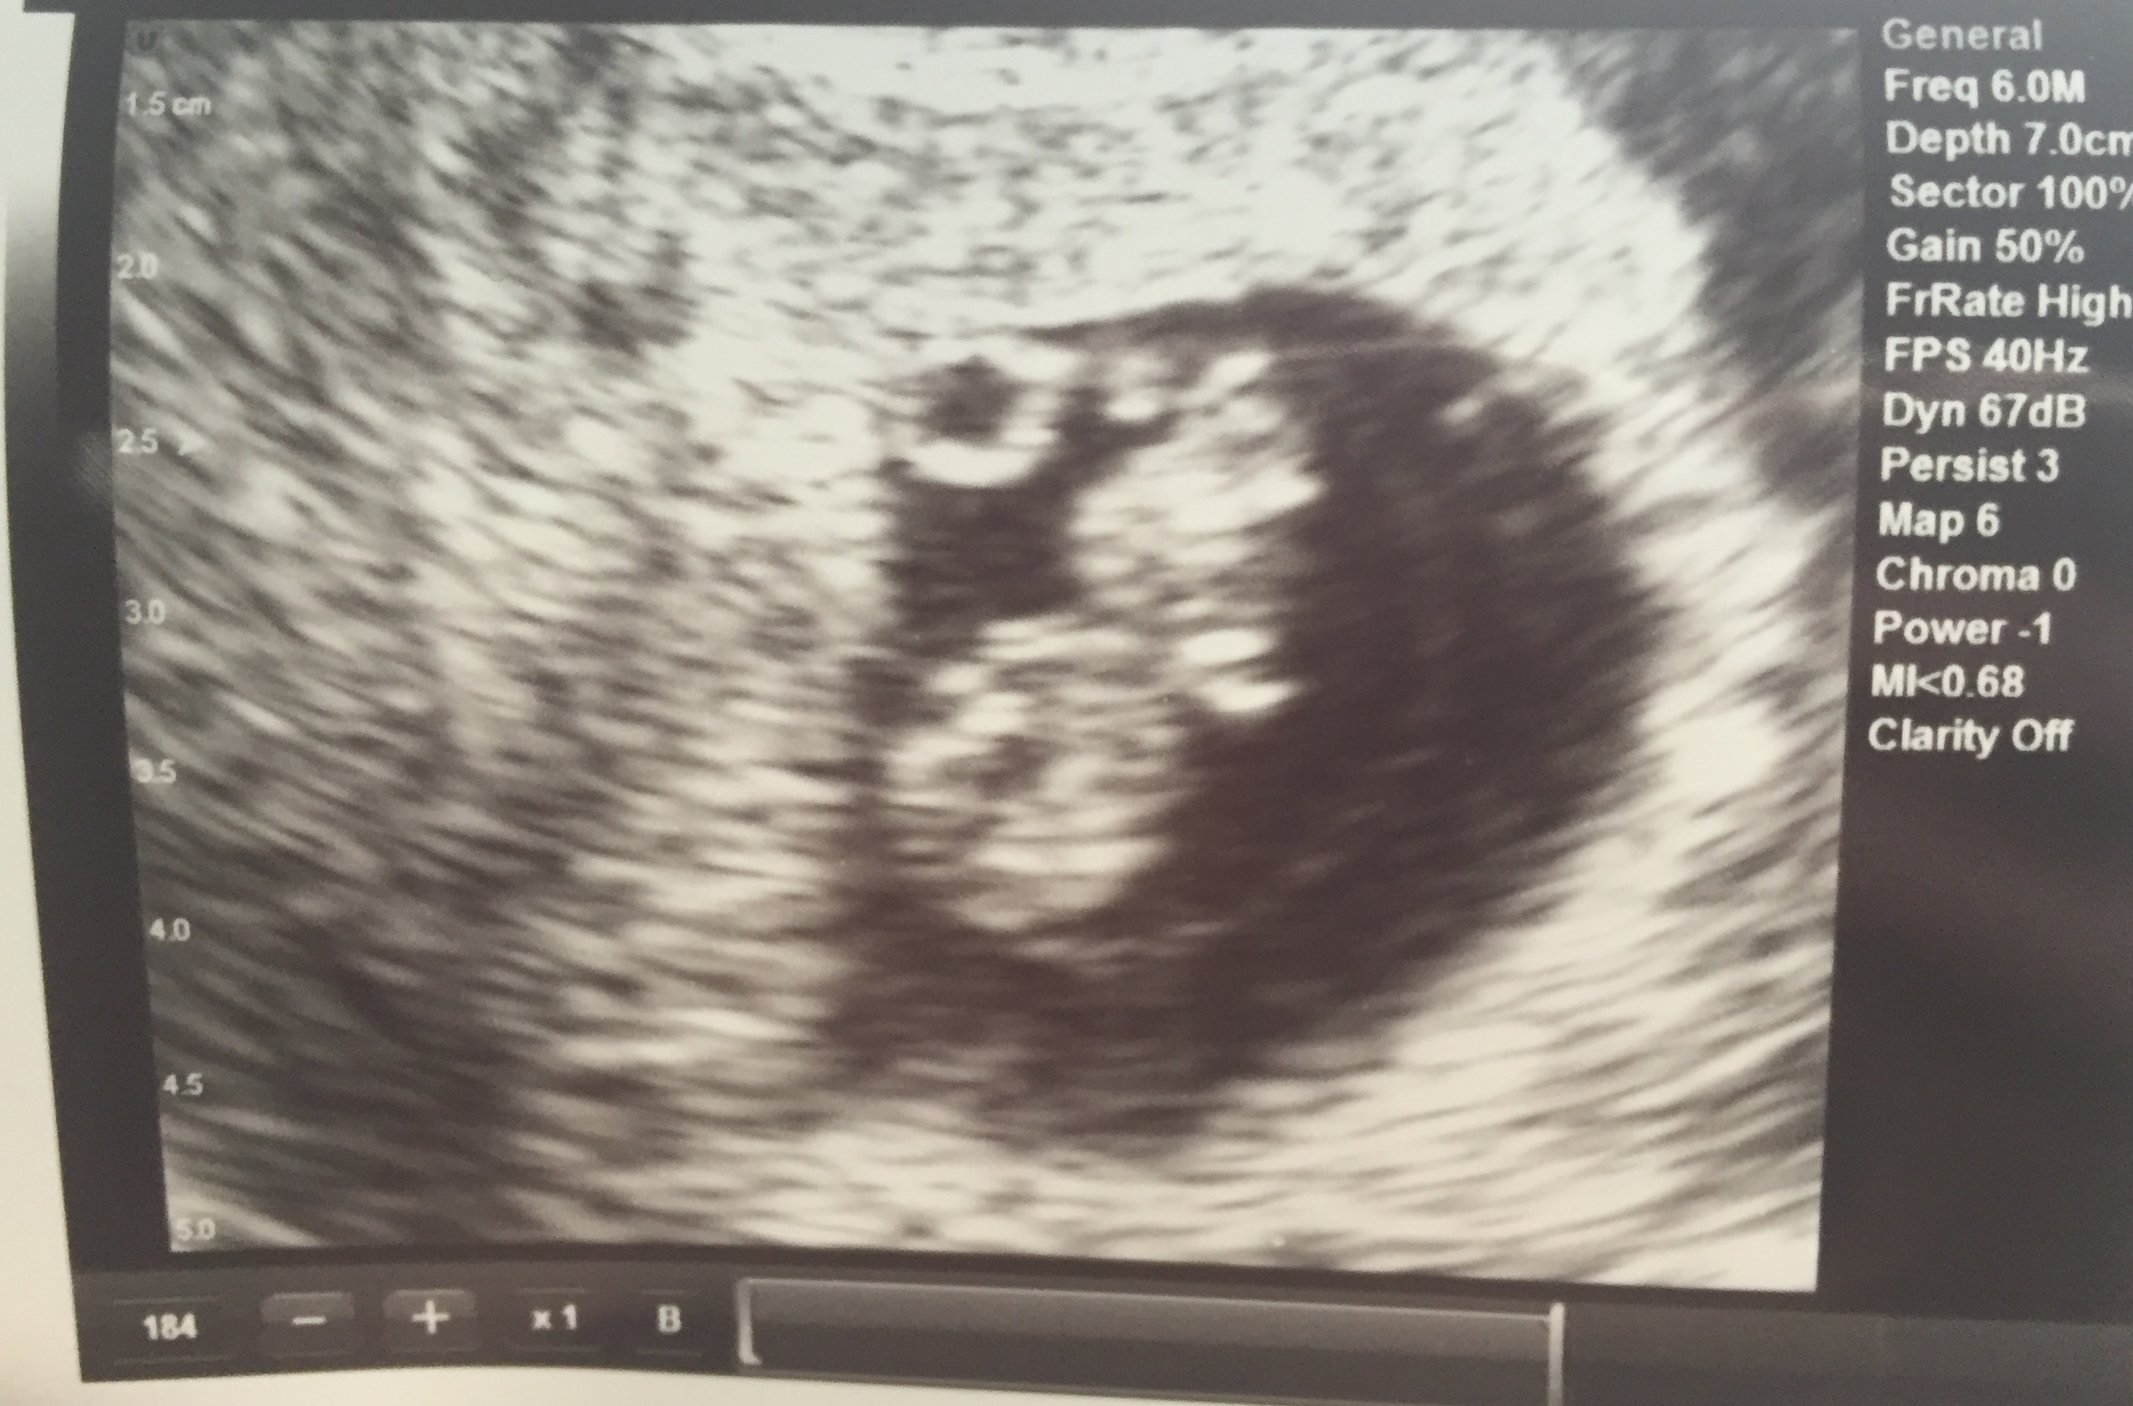

This was the blob as of today, 8 weeks. This was my first regular ultrasound instead of vaginal. I actually think I prefer vaginal because it is much clearer. But either way so happy to see it again. Heart rate was 169.